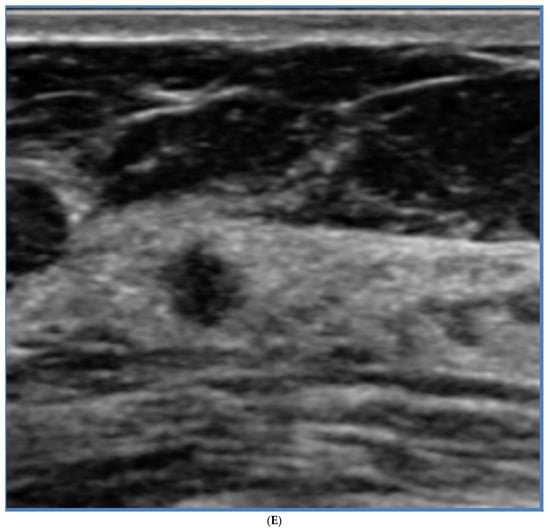

5. Ultrasound (US)